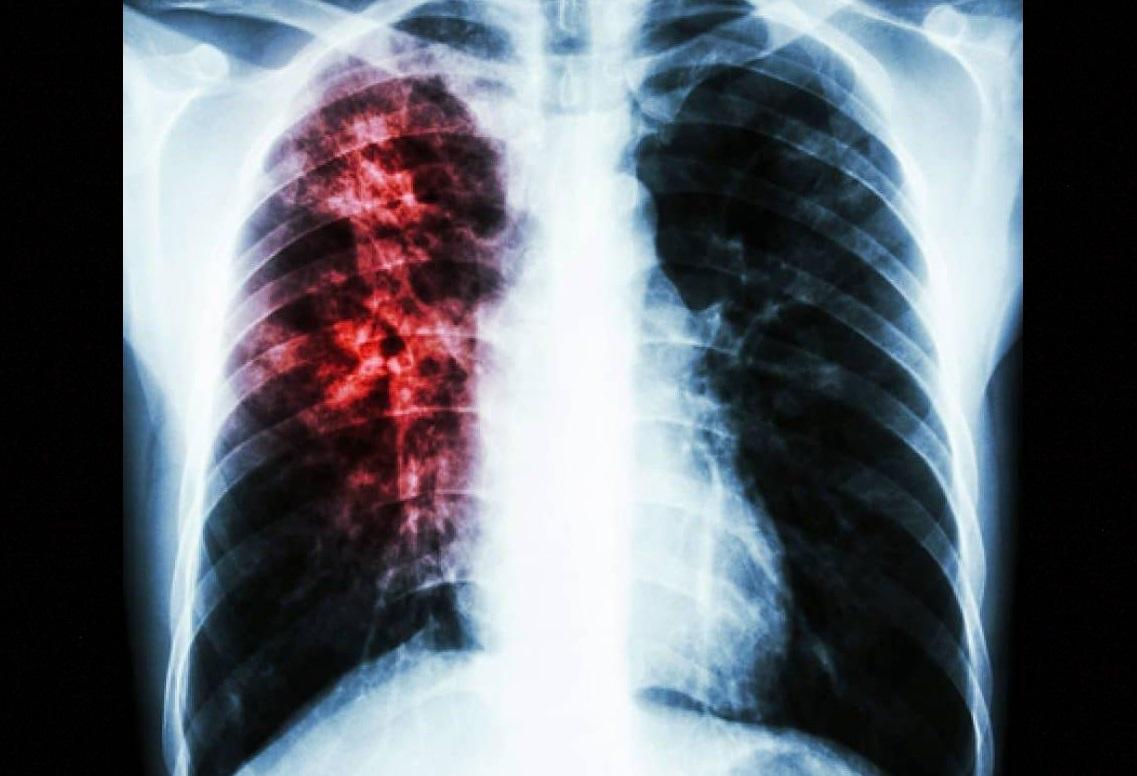

Caused by ‘Mycobacterium tuberculosis’ bacteria that most often affect the lungs, the disease can spread when people sick with TB expel bacteria into the air – for example by coughing.